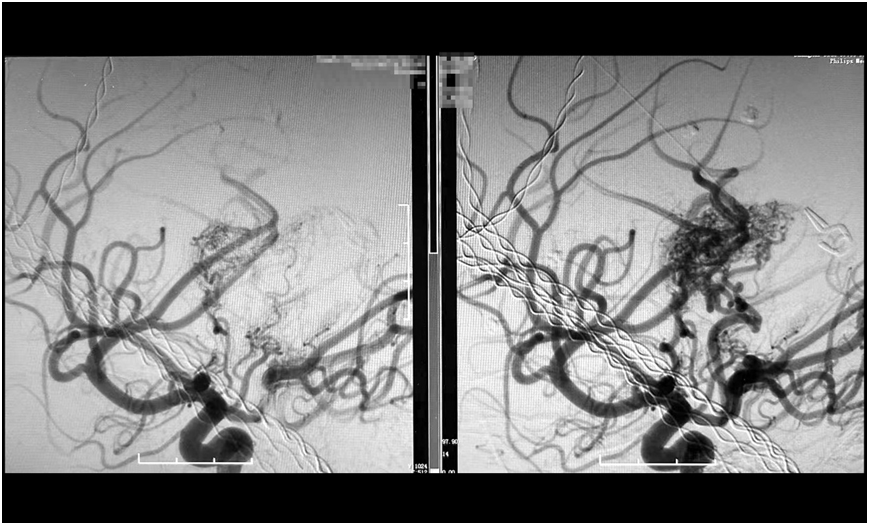

经过数小时的精雕细琢,手术团队成功栓塞预期目标责任血管。术后造影显示,假性动脉瘤已完全消失,畸形血管团达到预期栓塞效果,所有正常血管血流保持通畅(mTICI 3级)。

巨大脑动静脉畸形(右),被顺利栓塞(左)